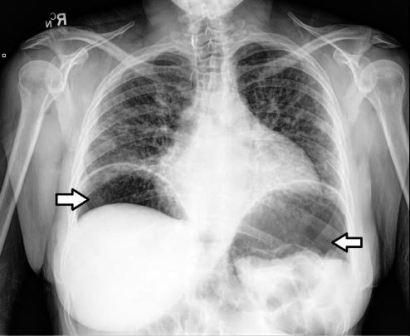

A 53-year-old white woman with schizophrenia was transferred from a psychiatric center after vague complaints of shortness of breath led to obtaining a chest x-ray film, which revealed significant subdiaphragmatic free air (Figure 1). On admission, the patient was alert and oriented; she insisted she was medically healthy and admitted only to mild abdominal distention. She denied current shortness of breath or any other GI complaints and further denied recent fever or chill. Her past history was significant for scleroderma and uncontrolled schizophrenia that resulted from nonadherence to prescribed aripiprazole.

CT scans of the patient’s chest, abdomen, and pelvis further detailed the pneumoperitoneum and showed intraluminal free air alongside gravity-defying intramural air in the small intestine, although there were no signs of perforation (Figure 2). Of note, the radiographs revealed esophageal stricture with proximal dilatation in addition to pneumoperitoneum, consistent with the patient’s diagnosis of scleroderma (Figure 3).